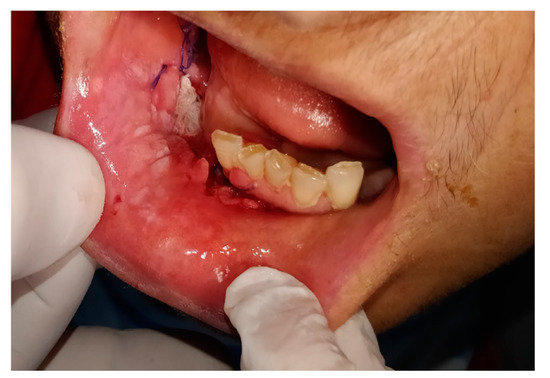

- the resolution of the video image to evaluate facial asymmetries, the presence of swellings, bone exposures, skin and mucous membrane changes due to the presence of suspected lesion was 89% satisfactory

- evaluate the surgical sites (possible presence of visible masses and/or local recurrences, evident lymphadenopathies, etc.),

| SubGroup B1 Neoplasm 1st visit | 12 contacts | Skin Carcinoma: 3 | Skin Biopsy: 2 |

| Mucosa Oral Carcinoma: 8 | Oral Biopsy: 4 | ||

| Submandibular gland Carcinoma: 1 | |||